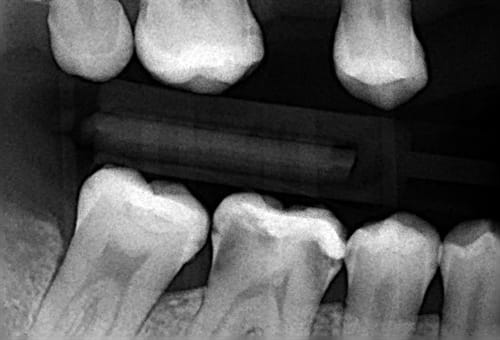

Voilà tout de même une dent que la majorité des intervenants ont jugé à extraire.

Avouez que c'est étonnant...